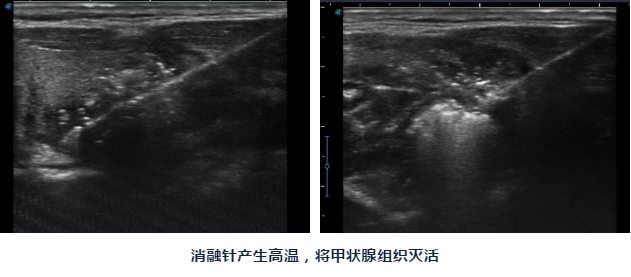

陈主任告诉她:对良性甲状腺结节,现在可以做微创消融治疗,只要局部麻醉,将一根消融针插入结节,通过消融针产生高温就可以将结节灭活,之后结节就会慢慢吸收、缩小。

陈主任说:甲状腺结节消融做完后脖子上只有一个针眼,术后也不影响活动、进食,同时手术是在超声引导下进行,只消融结节,能尽最大限度保护正常甲状腺组织,也可以清楚避开血管、气管、食管、神经等周边组织器官,术后出现声音嘶哑、出血、甲减的几率要小很多。